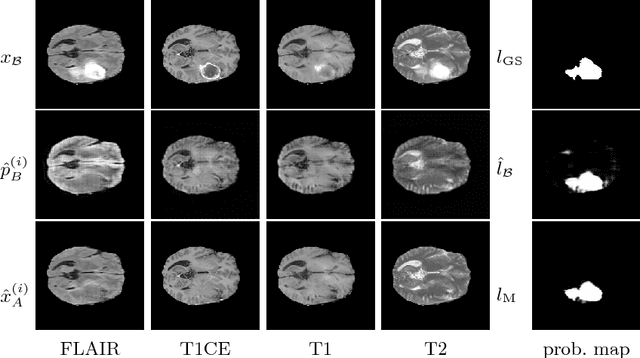

Abstract:We present a method to model pathologies in medical data, trained on data labelled on the image level as healthy or containing a visual defect. Our model not only allows us to create pixelwise semantic segmentations, it is also able to create inpaintings for the segmentations to render the pathological image healthy. Furthermore, we can draw new unseen pathology samples from this model based on the distribution in the data. We show quantitatively, that our method is able to segment pathologies with a surprising accuracy and show qualitative results of both the segmentations and inpaintings. A comparison with a supervised segmentation method indicates, that the accuracy of our proposed weakly-supervised segmentation is nevertheless quite close.